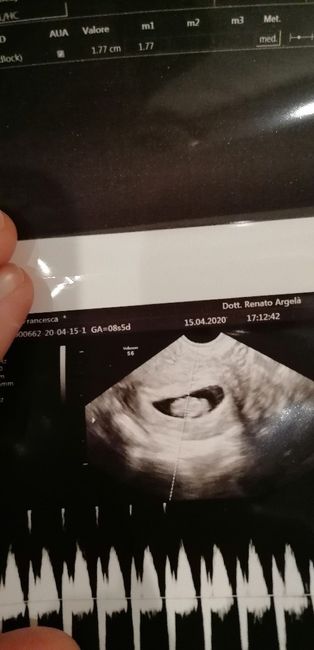

La prima ecografia a sinistra è della mia prima figlia che ora ha due anni, quella a destra l’ho fatta settimana scorsa. Dalla posizione a me parrebbe femmina anche la seconda, ma leggendo sembrerebbe che la placenta dovrebbe essere dall’altro lato.. insomma non ci ho capito molto!! Secondo voi? Le ecografie sono entrambe interne.